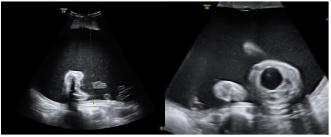

Beispiel 3: Massives, progressives Polyhydramnion. Magen nicht sicher darstellbar und im Halsbereich Pouch-Bildung bei einer Oesophagusatresie, wobei sich hier der Pouch retrograde via Fistel gefüllt hat.

Beispiel 4: Progressives Polyhydramnion und Makrosomie bedingt durch Hepatomegalie bei fetaler Anämie infolge Hyper-zirkulation. In der Plazenta sieht man multiple, echoleere Tumoren, welche Chorangiomen entsprechen.